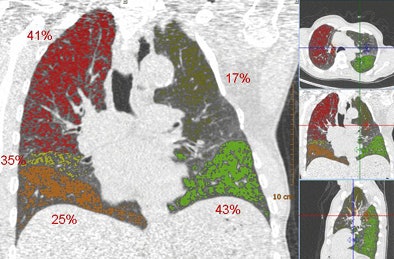

| Above, images from the expiration scan of a 65-year-old man with GOLD stage 3. The image shows increased density in some areas, common in expiration scans, but also regions that remain dark and are indicative of air trapping. Below, the overlay images from a single coronal section show that the left upper lobe is normal, while two lobes had emphysema and two had air trapping, indicating mixed-phenotype COPD. |

![]() |